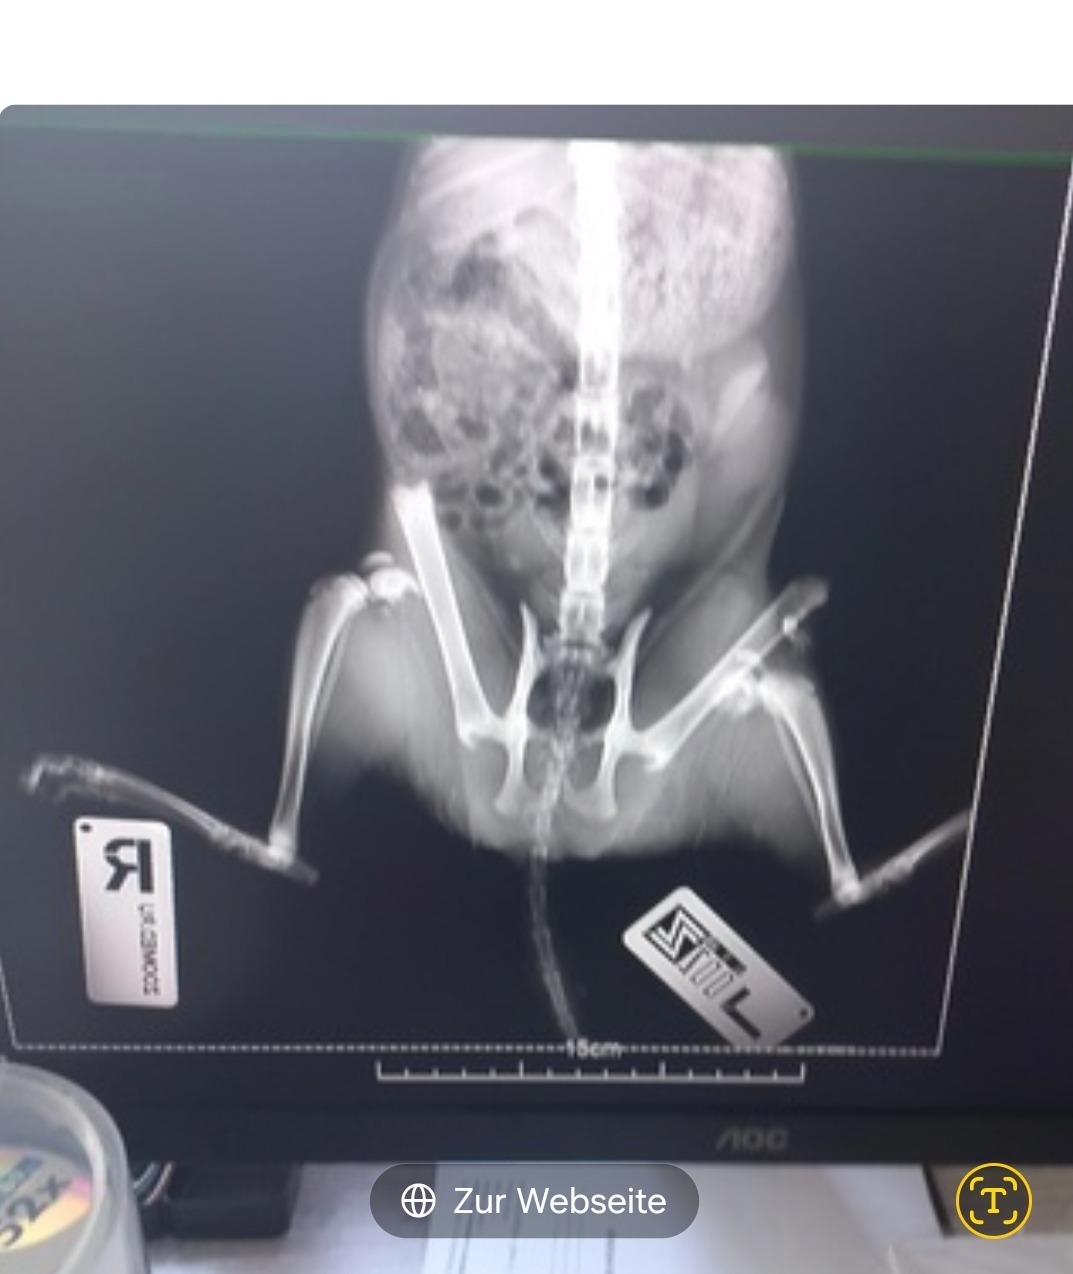

Die Behandlung dauerte insgesamt 3,5 Stunden – voller Anspannung, Sorge und Hoffnung. Es wurden Röntgenaufnahmen gemacht, um die Verletzungen genau zu erkennen, und schließlich wurde eine Operation durchgeführt. Die Ärztin war unglaublich einfühlsam und professionell. Sie erklärte mir, dass die kleine Katze noch eine Chance hat, wenn alles gut verläuft.